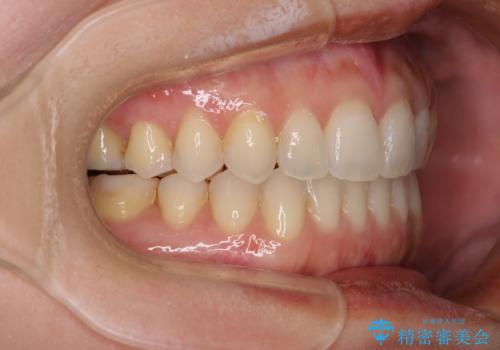

【モニター】狭い上顎歯列とオープンバイト 急速拡大装置を用いた矯正治療

- 前歯の開咬を気にして来院された患者様です。

上顎歯列が狭窄していたため、急速拡大装置により上顎骨を側方に拡大し、その後インビザラインにて矯正治療を行うこととしました。

舌の突出癖が開咬の原因であったので、改善のための舌トレーニングを行っていただきました。

舌トレーニングは後戻りにも大きく影響するため、とても重要なトレーニングです。